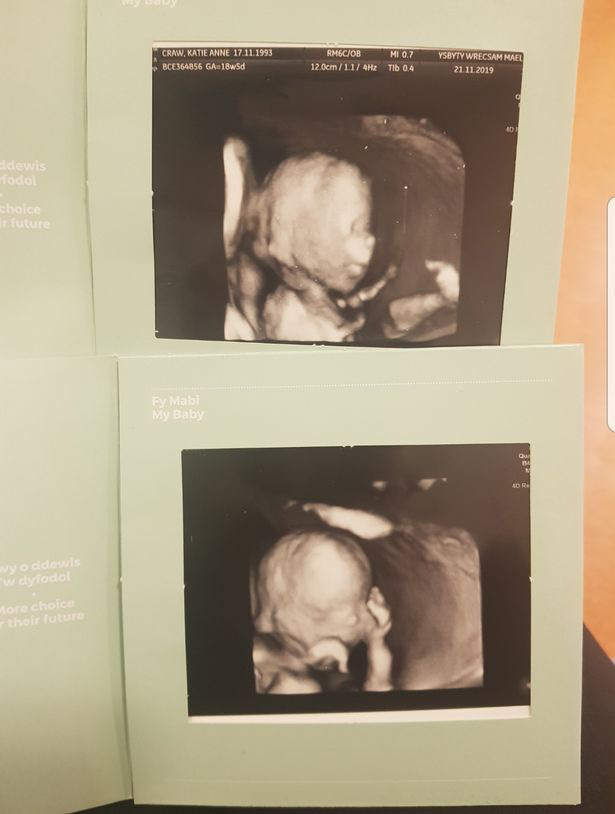

Song, trong lần siêu âm ở tuần thứ 12, các bác sĩ tại Bệnh viện Wrexham Maelor đã khiến chị bị sốc không nói nên lời khi thông báo chị sinh ba .

Siêu âm ở tuần 12 cho thấy chị Katie mang đa thai.

Hai tuần sau, hai vợ chồng chị Katie quay lại để siêu âm lần nữa, các bác sĩ vui mừng thông báo mỗi em bé đã có một túi ối riêng.

Cứ thế, bà mẹ này đều đặn đi khám thai hai tuần một lần để siêu âm xem các em bé phát triển có tốt không.